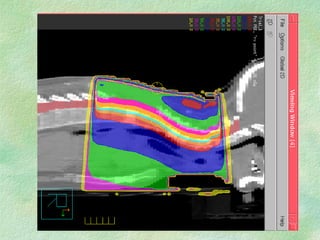

Example: neck: compensate to give uniform dose along midplane throughout treatment field

Uncompensated Compensated 15-20% <5%

Example: neck: compensateto give uniform dose along midplane throughout treatment field

• 52.